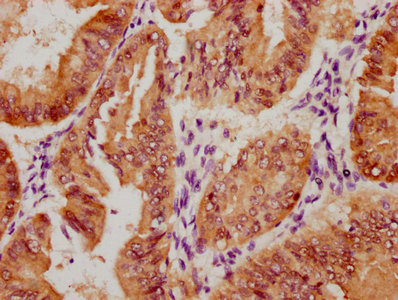

圖片:

應(yīng)用范圍:ELISA, IHC

Application Recommended Dilution IHC 1:20-1:200 -